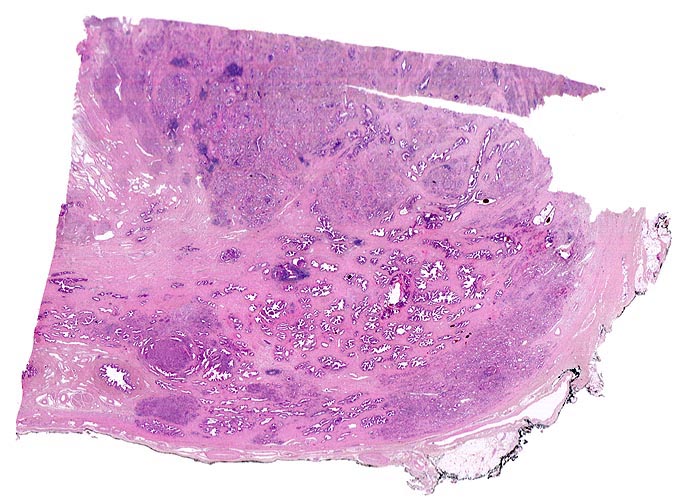

Adenokarzinom der Prostata

Multiple Karzinomherde infiltrieren das Prostatagewebe. Die normalen Drüsen sind deutlich grösser als die Karzinomdrüsen und enthalten in der Übersichtsvergrösserung erkennbare Lumina. Da die Karzinomdrüsen deutlich kleiner sind, erscheinen die Karzinomherde in der schwachen Vergrösserung als dunkle, unscharf begrenzte Flecken ohne erkennbare drüsige Strukturen.

Der Resektionsrand ist mit schwarzer Tusche markiert (schwarzer Streifen am Rand des Präparates).

Aufgrund eines deutlich erhöhten PSA Wertes anlässlich einer Screeninguntersuchung wurde die Prostata biopsiert. In 4 von 6 Stanzbiopsien von beiden Seiten waren Karzinominfiltrate nachweisbar. Daraufhin erfolgte eine radikale Prostatektomie.

Das Markieren des chirurgischen Resektionsrandes mit Tusche ermöglicht dem Pathologen festzustellen, ob der Tumor im Gesunden entfernt wurde. Die unvollständige Resektion kann einen fehlenden postoperativen Abfall des PSA auf Normalwerte erklären. Ein postoperativer Wiederanstieg des PSA zeigt bei einem unvollständig resezierten Tumor eher ein Lokalrezidiv an, beim vollständig resezierten Tumor eher eine Metastasierung.